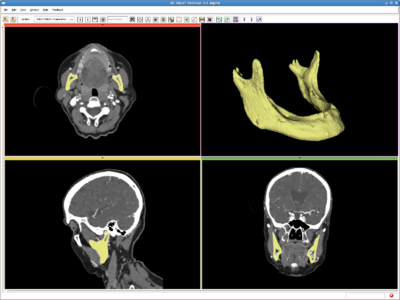

Multi-Object RSS (MORSS)

In contrast to the above single object RSS, in MORSS, the user can use different label (color) to draw the seed label image. After that, the algorithm detect the number of objects and evolve multiple contours simultaneously.

Use Cases, Examples

Meningioma

The testing image of this example can be downloaded at: File:RSS Grayscale.nrrd The label image is at: File:MORSS Grayscale-multilabel.nrrd